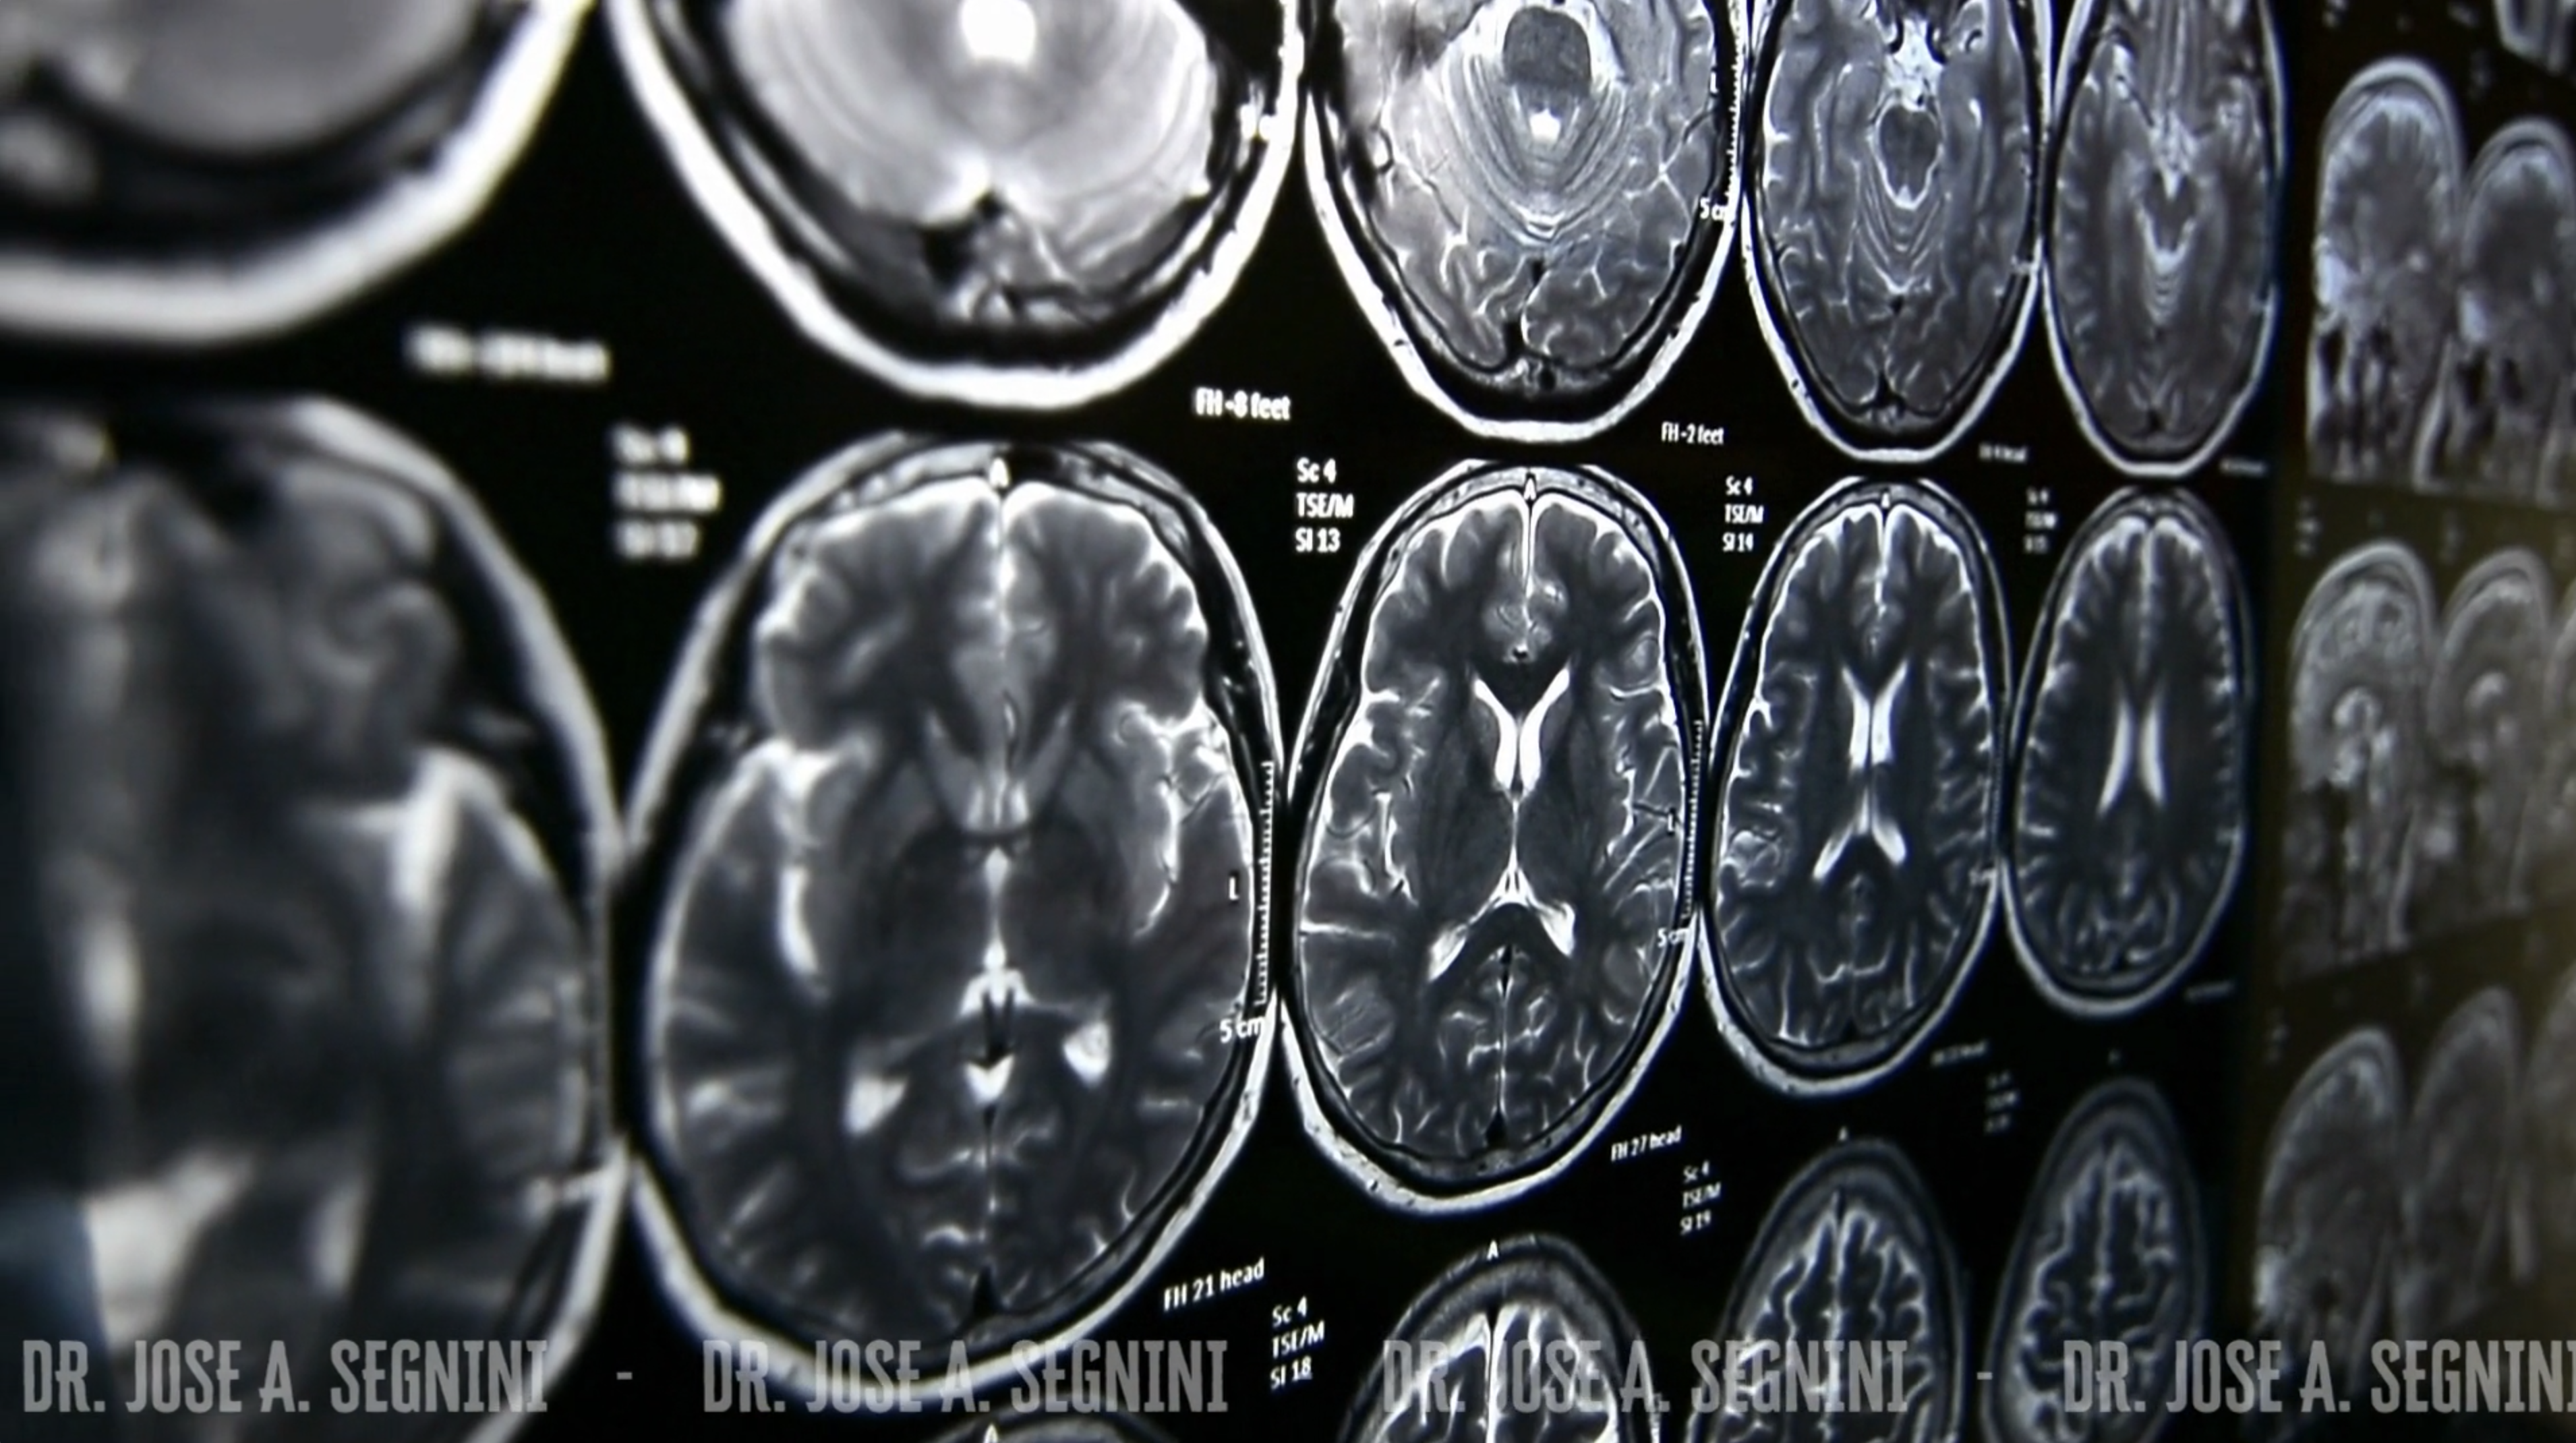

TELERADIOLOGIA

Sistemas de última tecnología para visualizar imágenes DICOM, gestionar servicios de radiología (RIS/PACS).

• Resonancia Magnética Nuclear